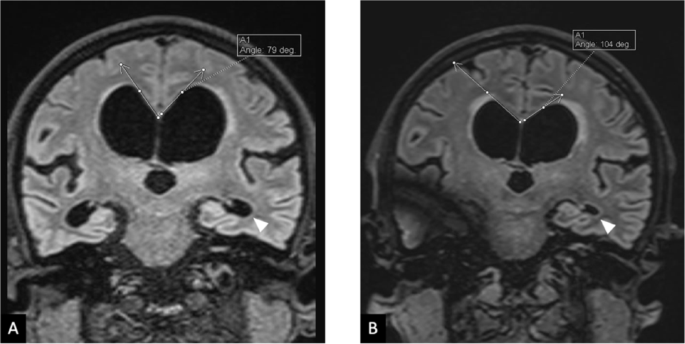

鉴于其认知、运动和泌尿系统症状的异常组合,怀疑存在器质性病因。脑部MRI显示脑室扩大,符合iNPH的特征(见图1)。患者接受了脑脊液分流手术。

2024年11月(A)分流手术前的冠状FLAIR图像和2025年6月(B)分流手术后的图像:(A) 脑积水(hydrocephalus);(B) 胼胝体边缘角(callosomarginal angle)恢复正常(>90度),颞角处的脑室扩张明显减轻(箭头所示)